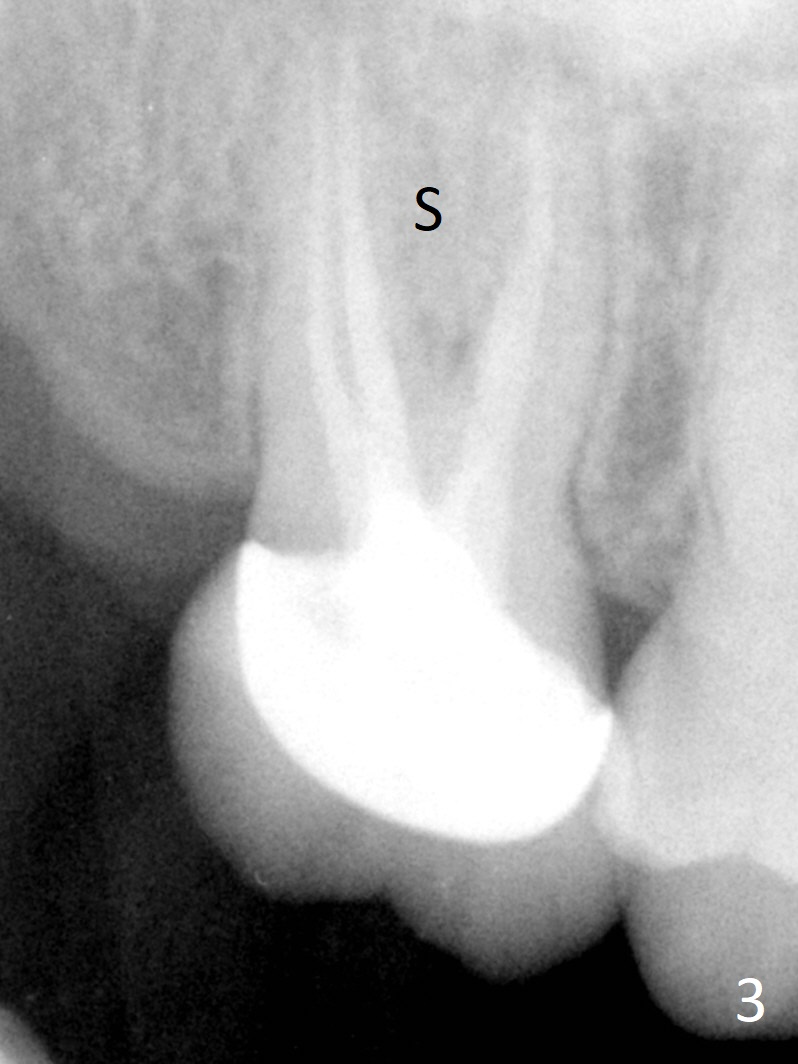

A 58-year-old woman has had RCT done at #2 for several years. The roots are trifurcated with sufficient bone height (Fig.1-3). Recently the tooth becomes symptomatic with formation of a distal fistula (Fig.4). After extraction, the septum (Fig.5 S) may be wide enough for initial drill (Fig.6). If not, resection the thin part of the septum (Fig.7 red line, with small or medium Rongeur) and use the initial drill (Fig.8). Anyway, take PA immediately to avoid sinus membrane perforation. If possible, adopt single drill technique.